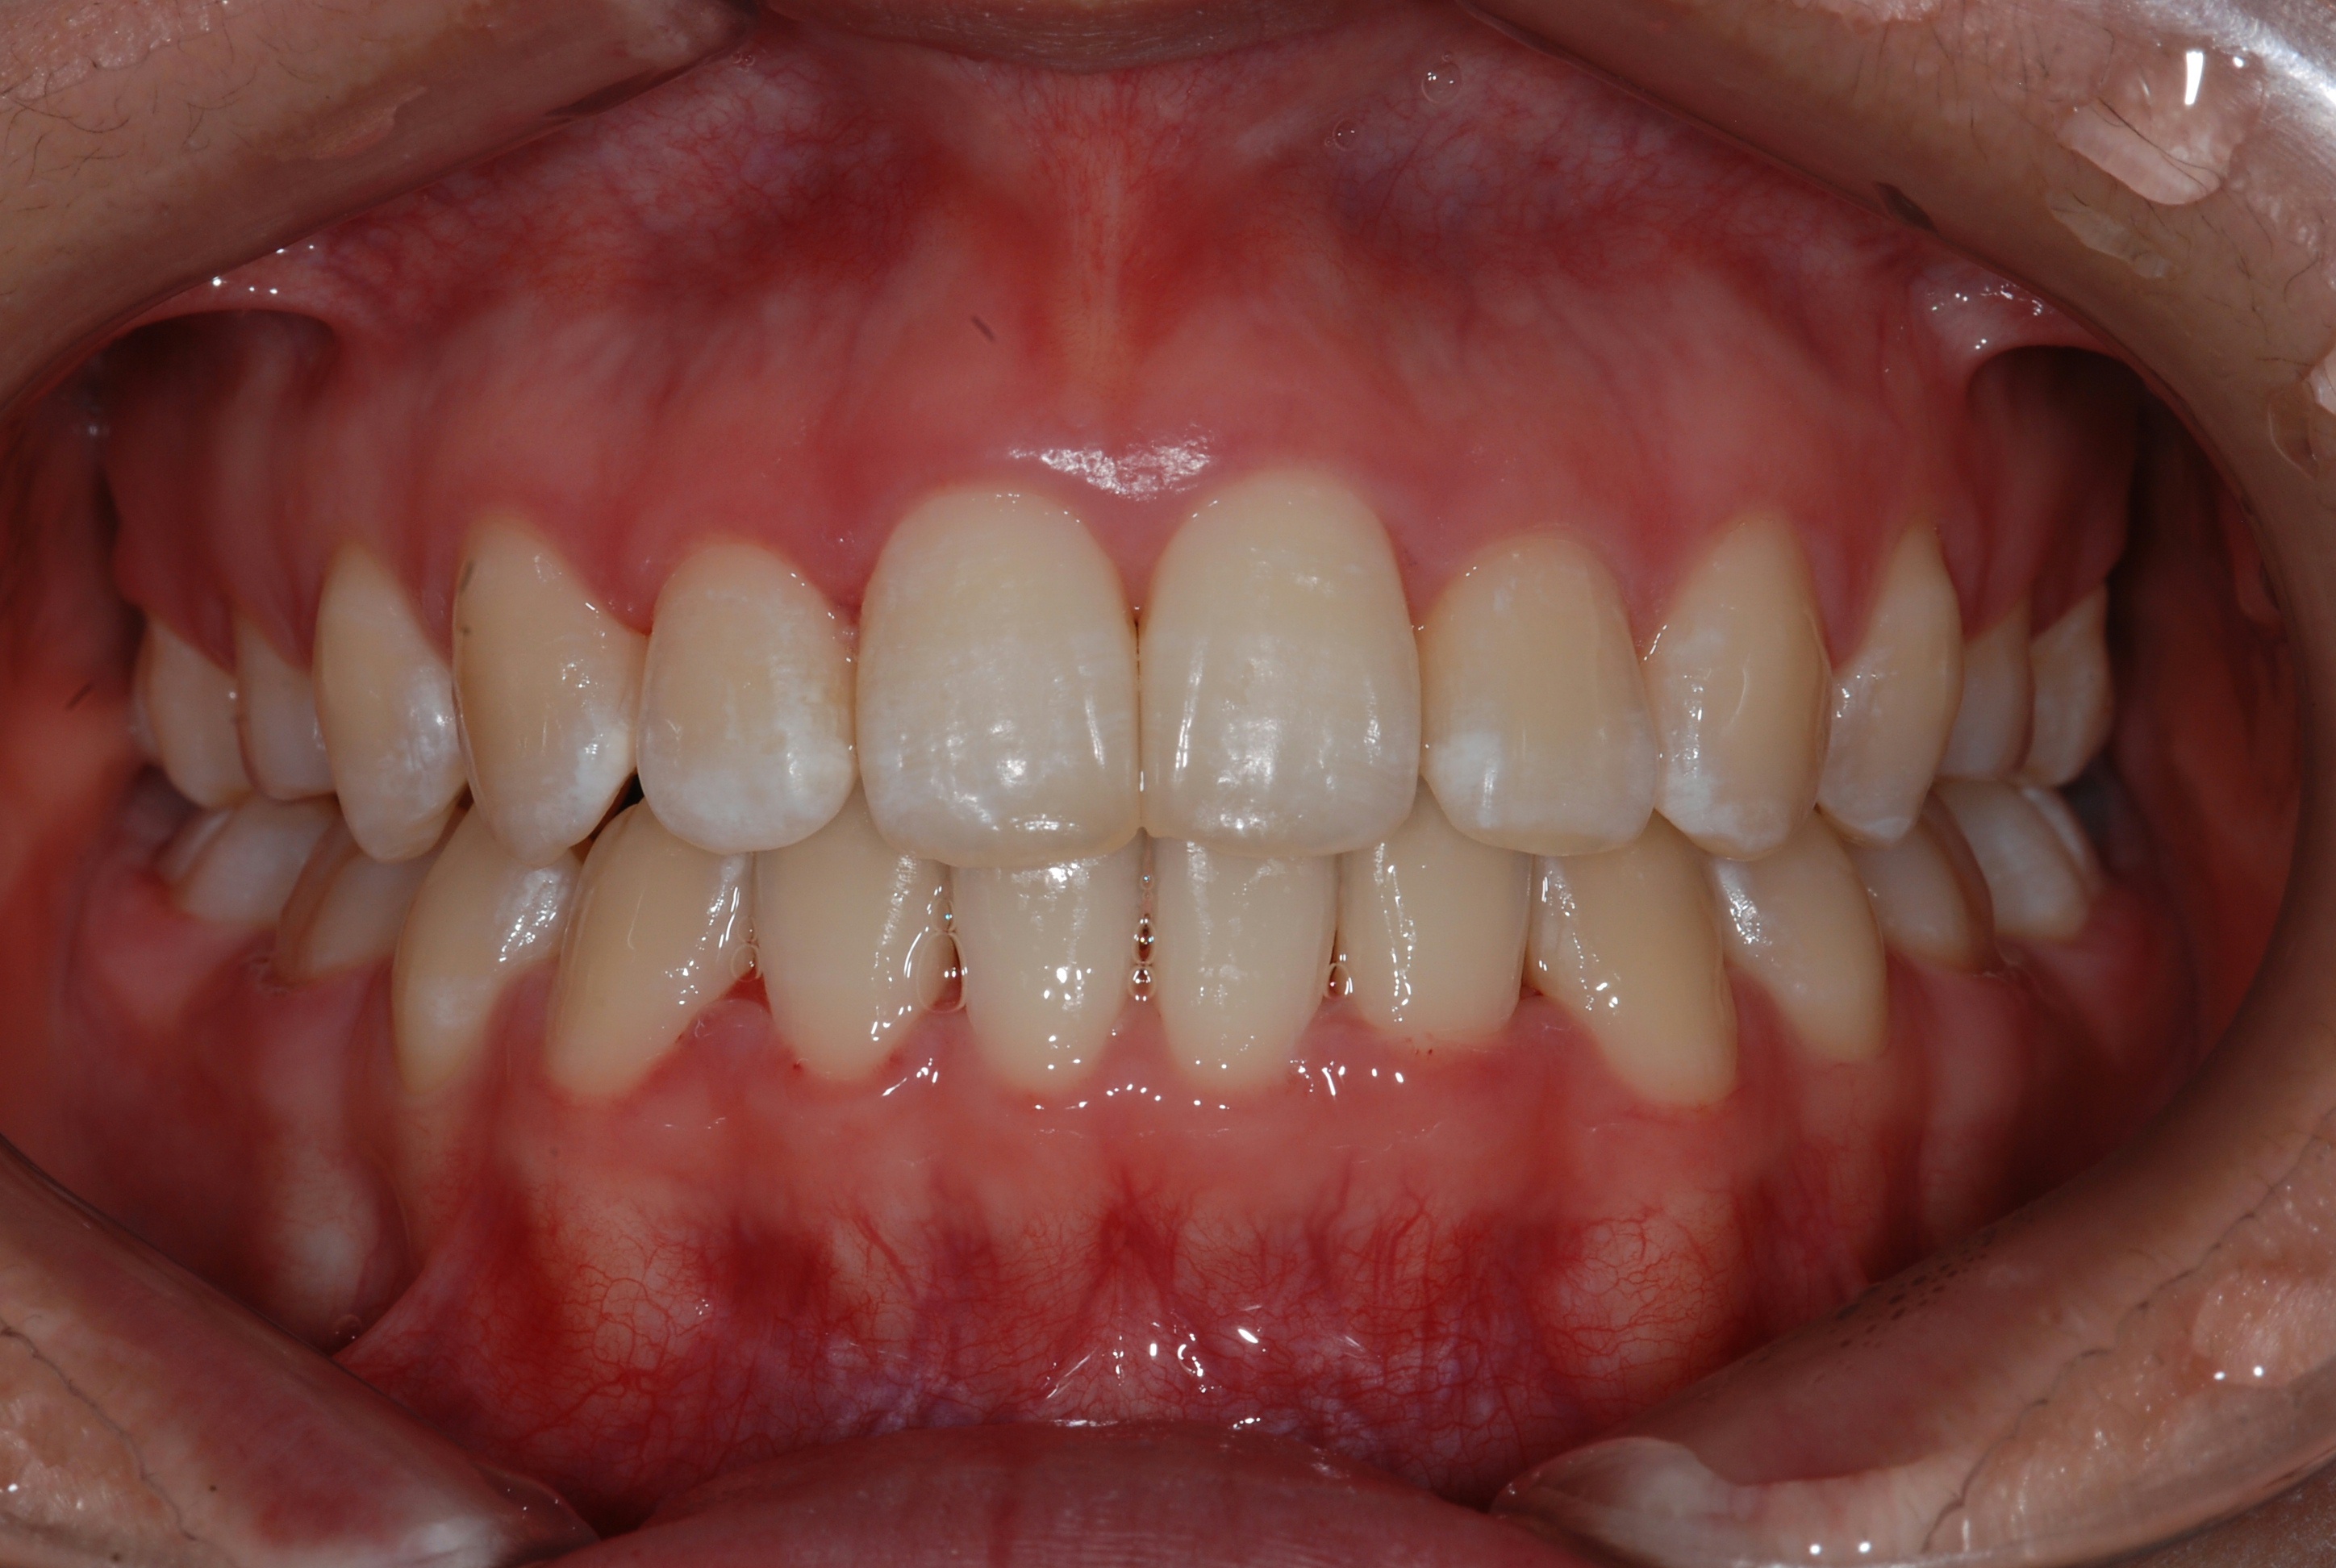

치료 후 사진입니다.